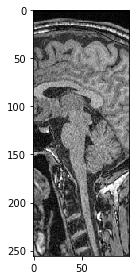

Nous pouvons également sélectionner un plan où tous les pixels ont la même position Y. Nous devons juste spécifier que nous souhaitons conserver tous les pixels en Z en utilisant la syntaxe :.

slice_image = image[:, 100]

imshow(slice_image)

<matplotlib.image.AxesImage at 0x2b54f836af0>

../_images/ad292cbffaab643c3d9273781ac2d7a8cb9aeed56d351d1c201b74c79fcbef31.png